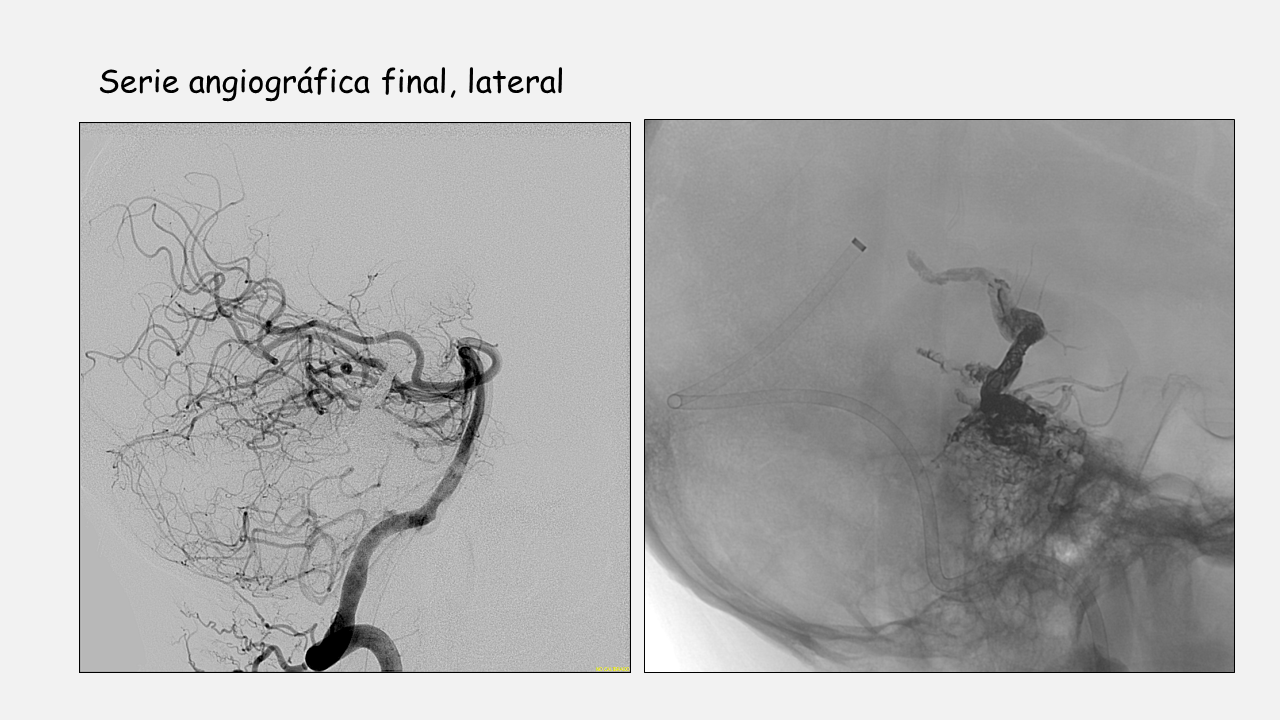

Estrategia y resumen de la intervención.

- MAV rota con aneurisma de flujo y nidal (elevado riesgo de resangrado) dependientes de arterias perforantes de difícil cateterismo.

- Al presentar una vena de drenaje única se procede a la embolización vía venosa utilizando microcatéter con punta desprendible y técnica de olla a presión.

- El objetivo de la embolización es que el agente embolizante ocluya el pie de vena con el menor reflujo posible y penetre en el nidus y en la parte distal de los pedículos arteriales para evitar sangrados postembolización.

- El pie de vena no es ciego por lo que se emboliza su trayecto distal para evitar la progresión del agente embolizante hacia esa vena.

- Posteriormente se colocan coils en la parte proximal de la vena y se inicia la inyección de agente embolizante de mayor densidad (18) hasta que se rellena todo el pie de vena. En este momento se inyecta pegamento al 50% para sellar la zona venosa donde están los coils y la parte proximal libre de coils (Técnica de la olla a presión).

- Se continúa la inyección de agente embolizante de menor densidad (12) que penetra en el nidus (se observa relleno y cierre del aneurisma nidal) y progresa hacia los pedículos arteriales (se observa desaparición por efecto de flujo del aneurisma de flujo en a. perforante).

- No se identifica reflujo hacia el pedículo de la AICA y en las series de control se identifica resto de MAV en esa zona por lo que, para evitar sangrados postembolización, se procede a la embolización vía arterial del pedículo dependiente de la AICA.